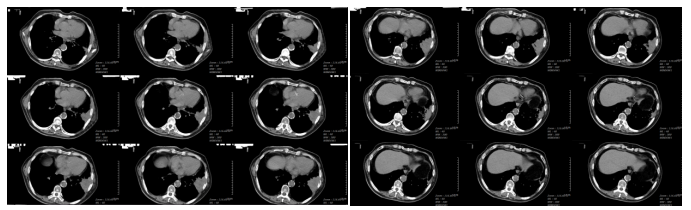

Chest CT on January 20, 2024 (during carbon ion therapy):Left lung tumor 8.0 × 4.6 × 5.3 cm